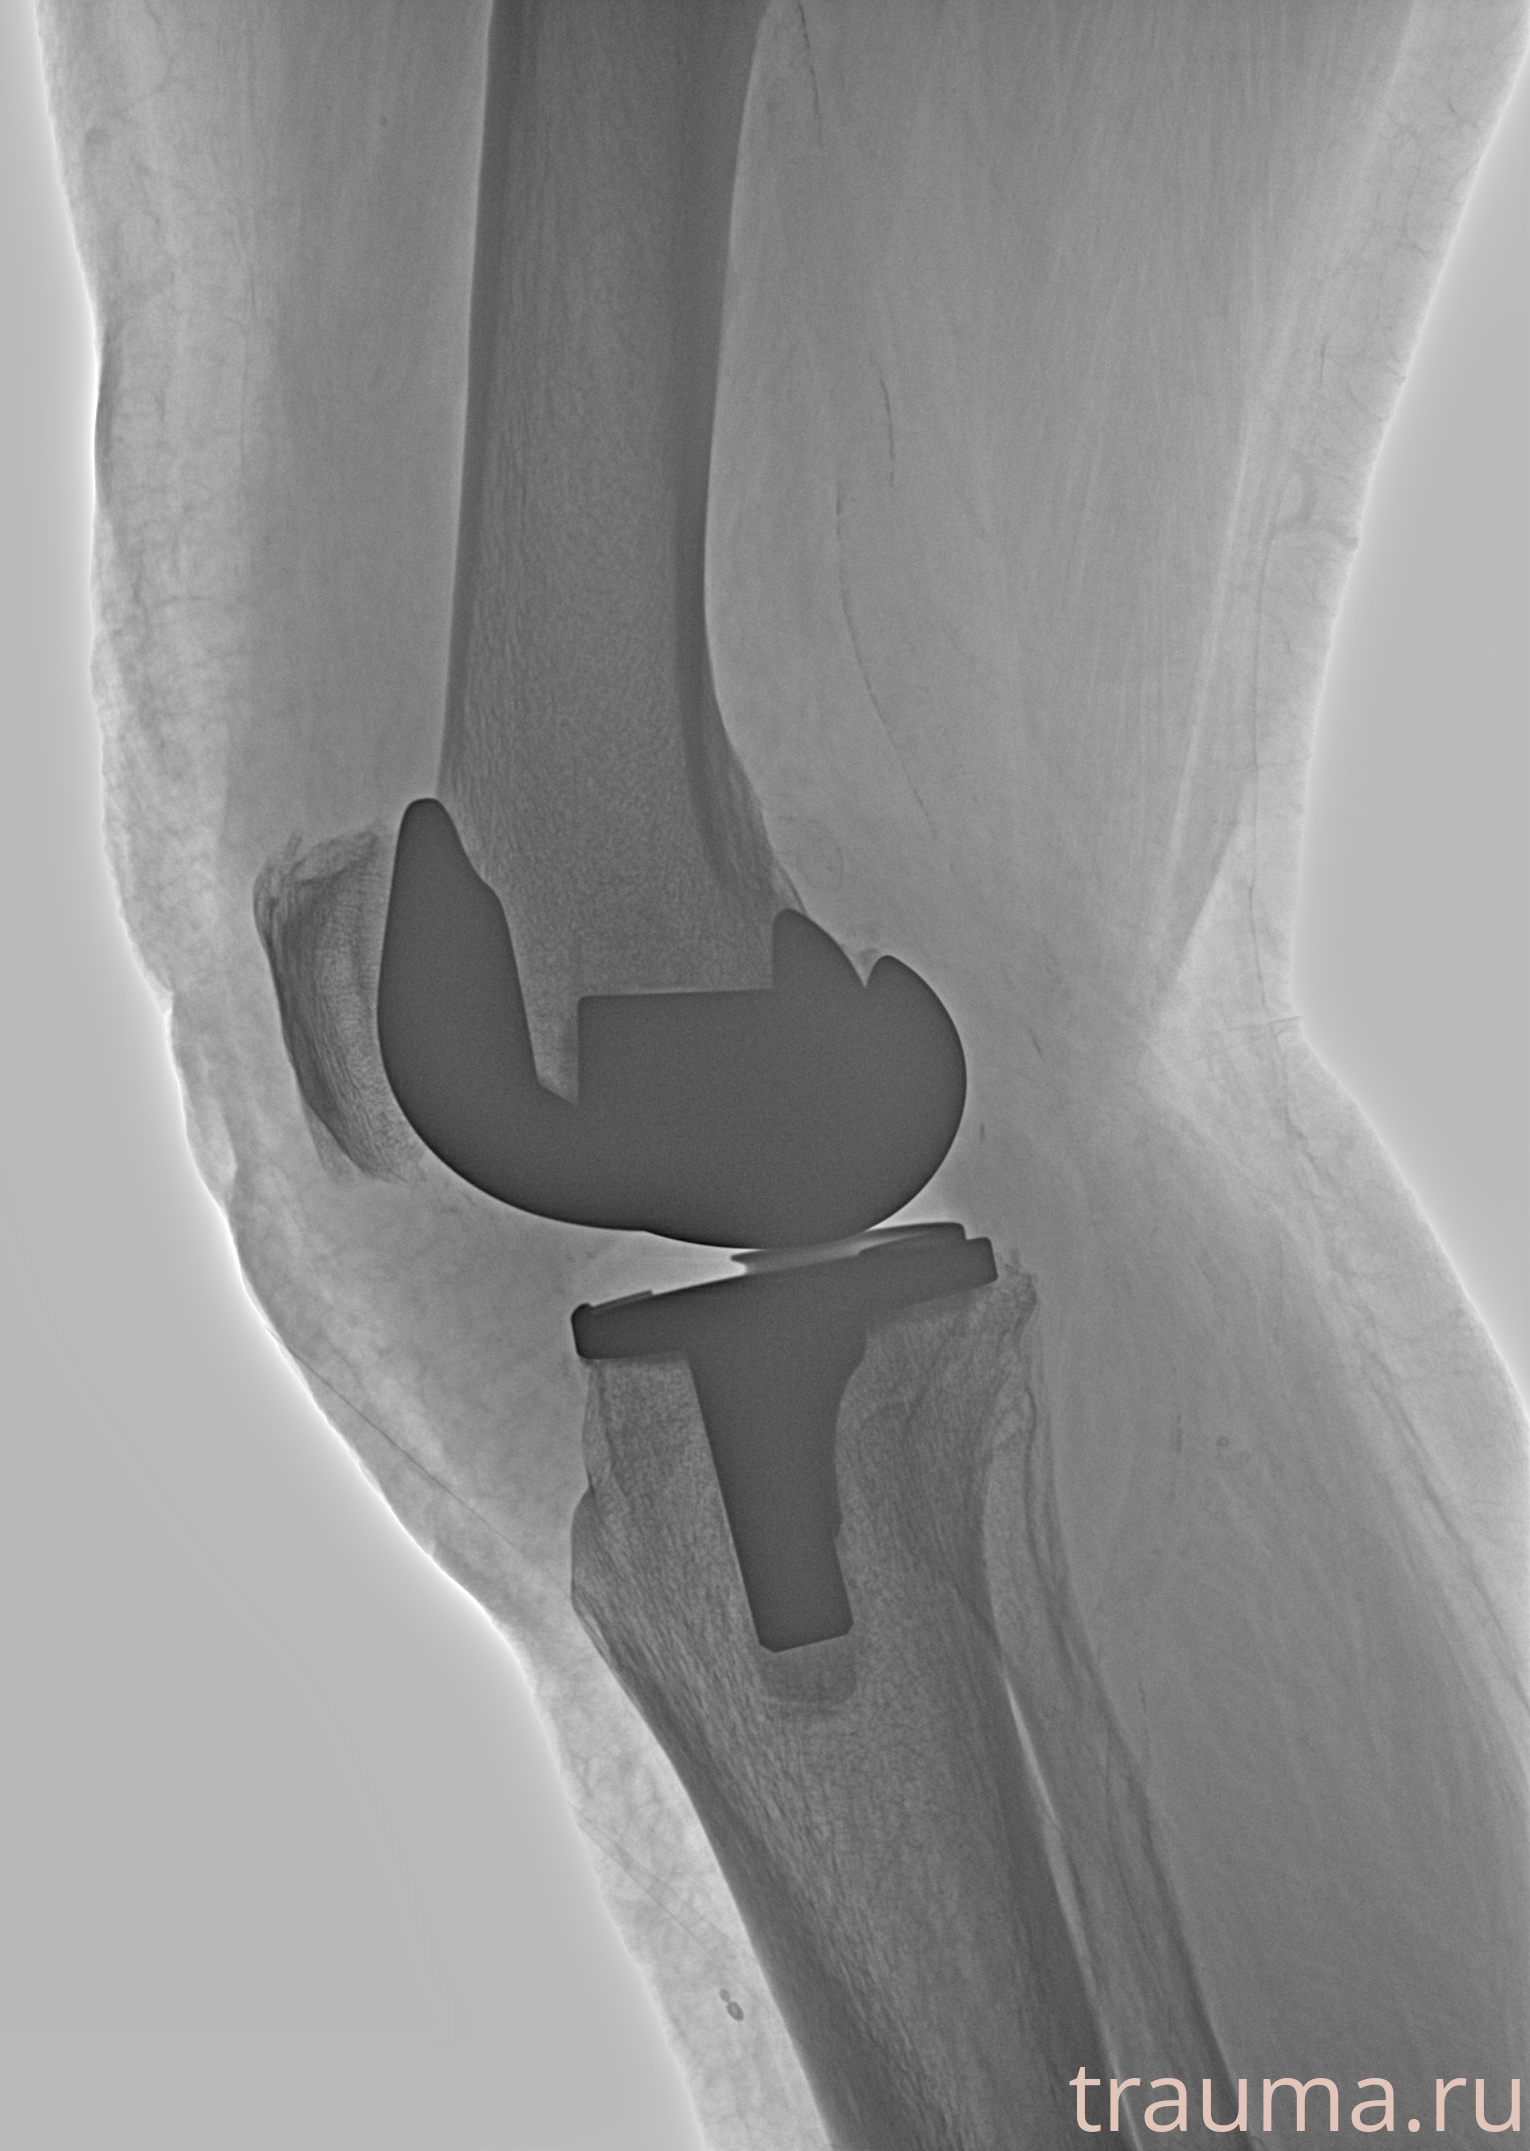

Правый

Рентгенограммы